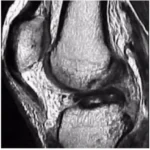

Lesão do Ligamento Cruzado Anterior (LCA) do Joelho

O ligamento cruzado anterior (LCA) é o principal estabilizador do joelho, impedindo o deslocamento anterior da tíbia em relação ao fêmur. Pacientes com lesão do LCA frequentemente relatam um episódio de entorse ou trauma no joelho, seguido de inchaço, dor e, posteriormente, sensação de falseio.

A instabilidade causada por essa lesão pode levar a lesões degenerativas da cartilagem articular a partir de 6 meses. Após 5 anos de lesão, 50% dos pacientes desenvolvem artrose no joelho, e após 10 anos, 75% apresentam esse quadro.

Em 50% dos casos, pacientes com lesão do LCA também possuem lesões meniscais associadas, sendo mandatório investigar essas ocorrências. O exame clínico, com testes como Lachmann e Pivot Shift, possui alta acurácia no diagnóstico.

Tratamento

Atualmente, a indicação de tratamento para indivíduos fisicamente ativos que apresentam instabilidade anterior do joelho é a reconstrução ligamentar com enxertos. Os enxertos mais utilizados são os tendões da pata de ganso (semitendinoso e grácil) e o tendão patelar.

A reconstrução do LCA com tendões flexores (grácil e semitendinoso) é uma técnica que apresenta menor morbidade, pós-operatório menos doloroso e melhor estética, por não envolver um acesso anterior no joelho. Funcionalmente, os enxertos mencionados são equivalentes e têm respaldo na literatura.